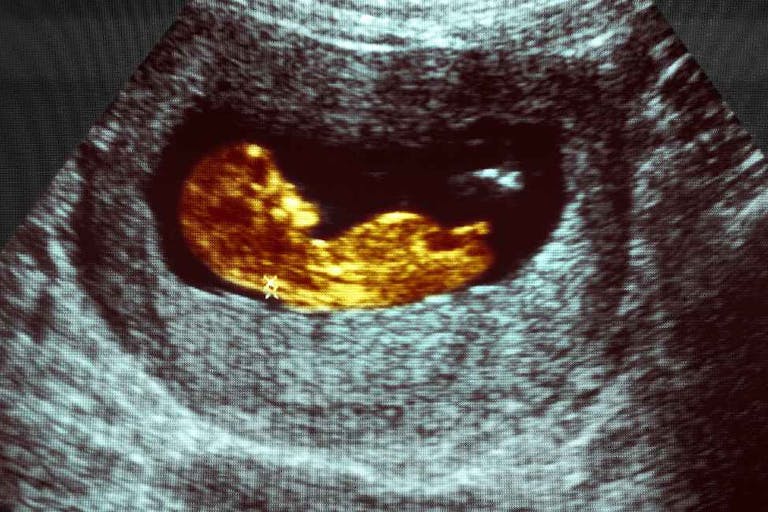

Florida’s Supreme Court has ruled that a law protecting preborn children from abortion after 15 weeks gestation can take effect. This means that a law protecting preborn children from abortion from six weeks gestation onward will also be allowed to take effect. However, the court also ruled that an initiative to make abortion a constitutional right in the state can be placed on the November ballot.

HB 5, or the Reducing Fetal and Infant Mortality bill, was signed by Governor Ron DeSantis in April of 2022; an injunction was placed on the law, but it was thrown out, and the Supreme Court agreed to hear the case. In 2023, lawmakers signed HB 7, or the Heartbeat Protection Act, into law, which protects children from abortion after six weeks gestation. It was specifically written to only take effect if the Supreme Court upheld HB 5.

HB 7 will therefore take effect in 30 days.